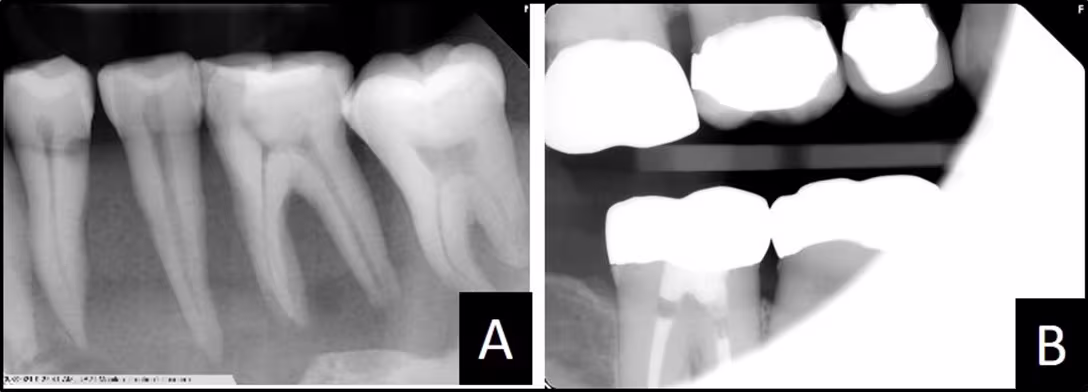

There are consequences when the path of radiation does not contain the teeth and the full sensor: if the sensor and the required teeth are not in the radiation’s path, they will not appear on the image (Figure 2A) and if the path of radiation does not cover the entire sensor, a cone-cut (an area of non-exposure) will result (Figure 2B)

Figure 2

(A) Active sensor was not behind the canine.

(B) Sensor not fully covered by radiation resulted in a cone-cut.